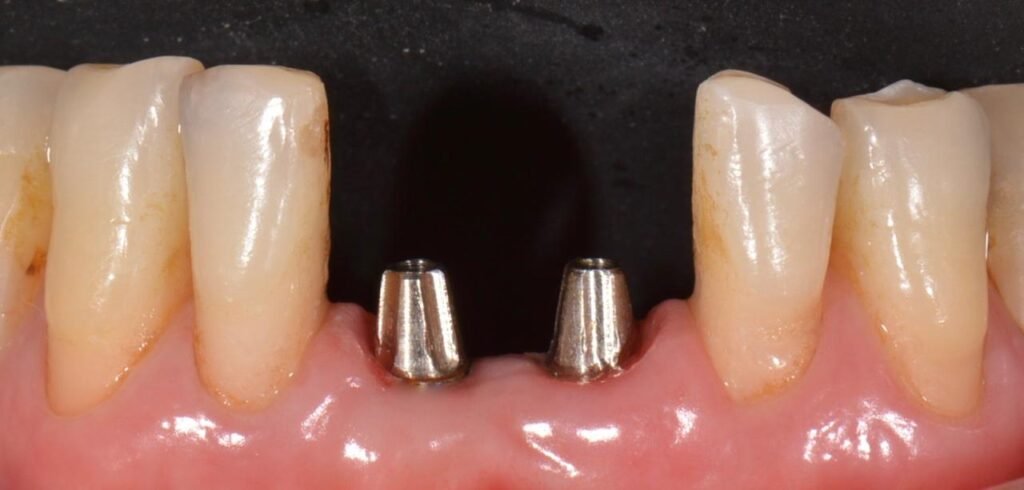

Utilizando as técnicas de acordo com classificação proposta, é possível construir um parede vestibular que se mantém íntegra ao longo do tempo, mantendo a estética dos casos e tornando os implantes imediatos uma alternativa segura independente da situação da tábua óssea vestibular do alvéolo.